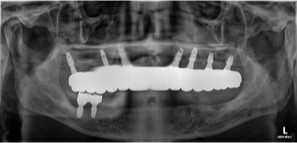

여러가지 요인으로 인해 문제가 생긴 기존 임플란트를 제거하고 새로운 임플란트를 식립하는 임플란트 재수술은 세심한 진단과 의료진의 풍부한 경험이 필요합니다.

많은 임상을 하다 보면 쓰시던 임플란트가 망가져서 다시 수술해야하는 경우를 많이 보게됩니다. 임플란트 주위의 뼈가 녹았거나 임플란트 자체가 파손된 경우도 있습니다.

바른이치 치과의 임플란트 재수술은 풍부한 임플란트 재수술 임상경험의 15년 이상 경력의 구강악안면외과 전문의 대표원장이 임플란트가 실패할 수 있는 모든 경우에 대응합니다.

1. 망가진 임플란트를 제거할 수 있는 특수 키트, 실패한 임플란트를 제거하고 정밀하고 세심한 진단으로 이전의 임플란트가 망가진 원인을 분석하여 기존의 임플란트를 오래 쓰실 수 있는 임플란트로 대체해 드리고 있습니다.